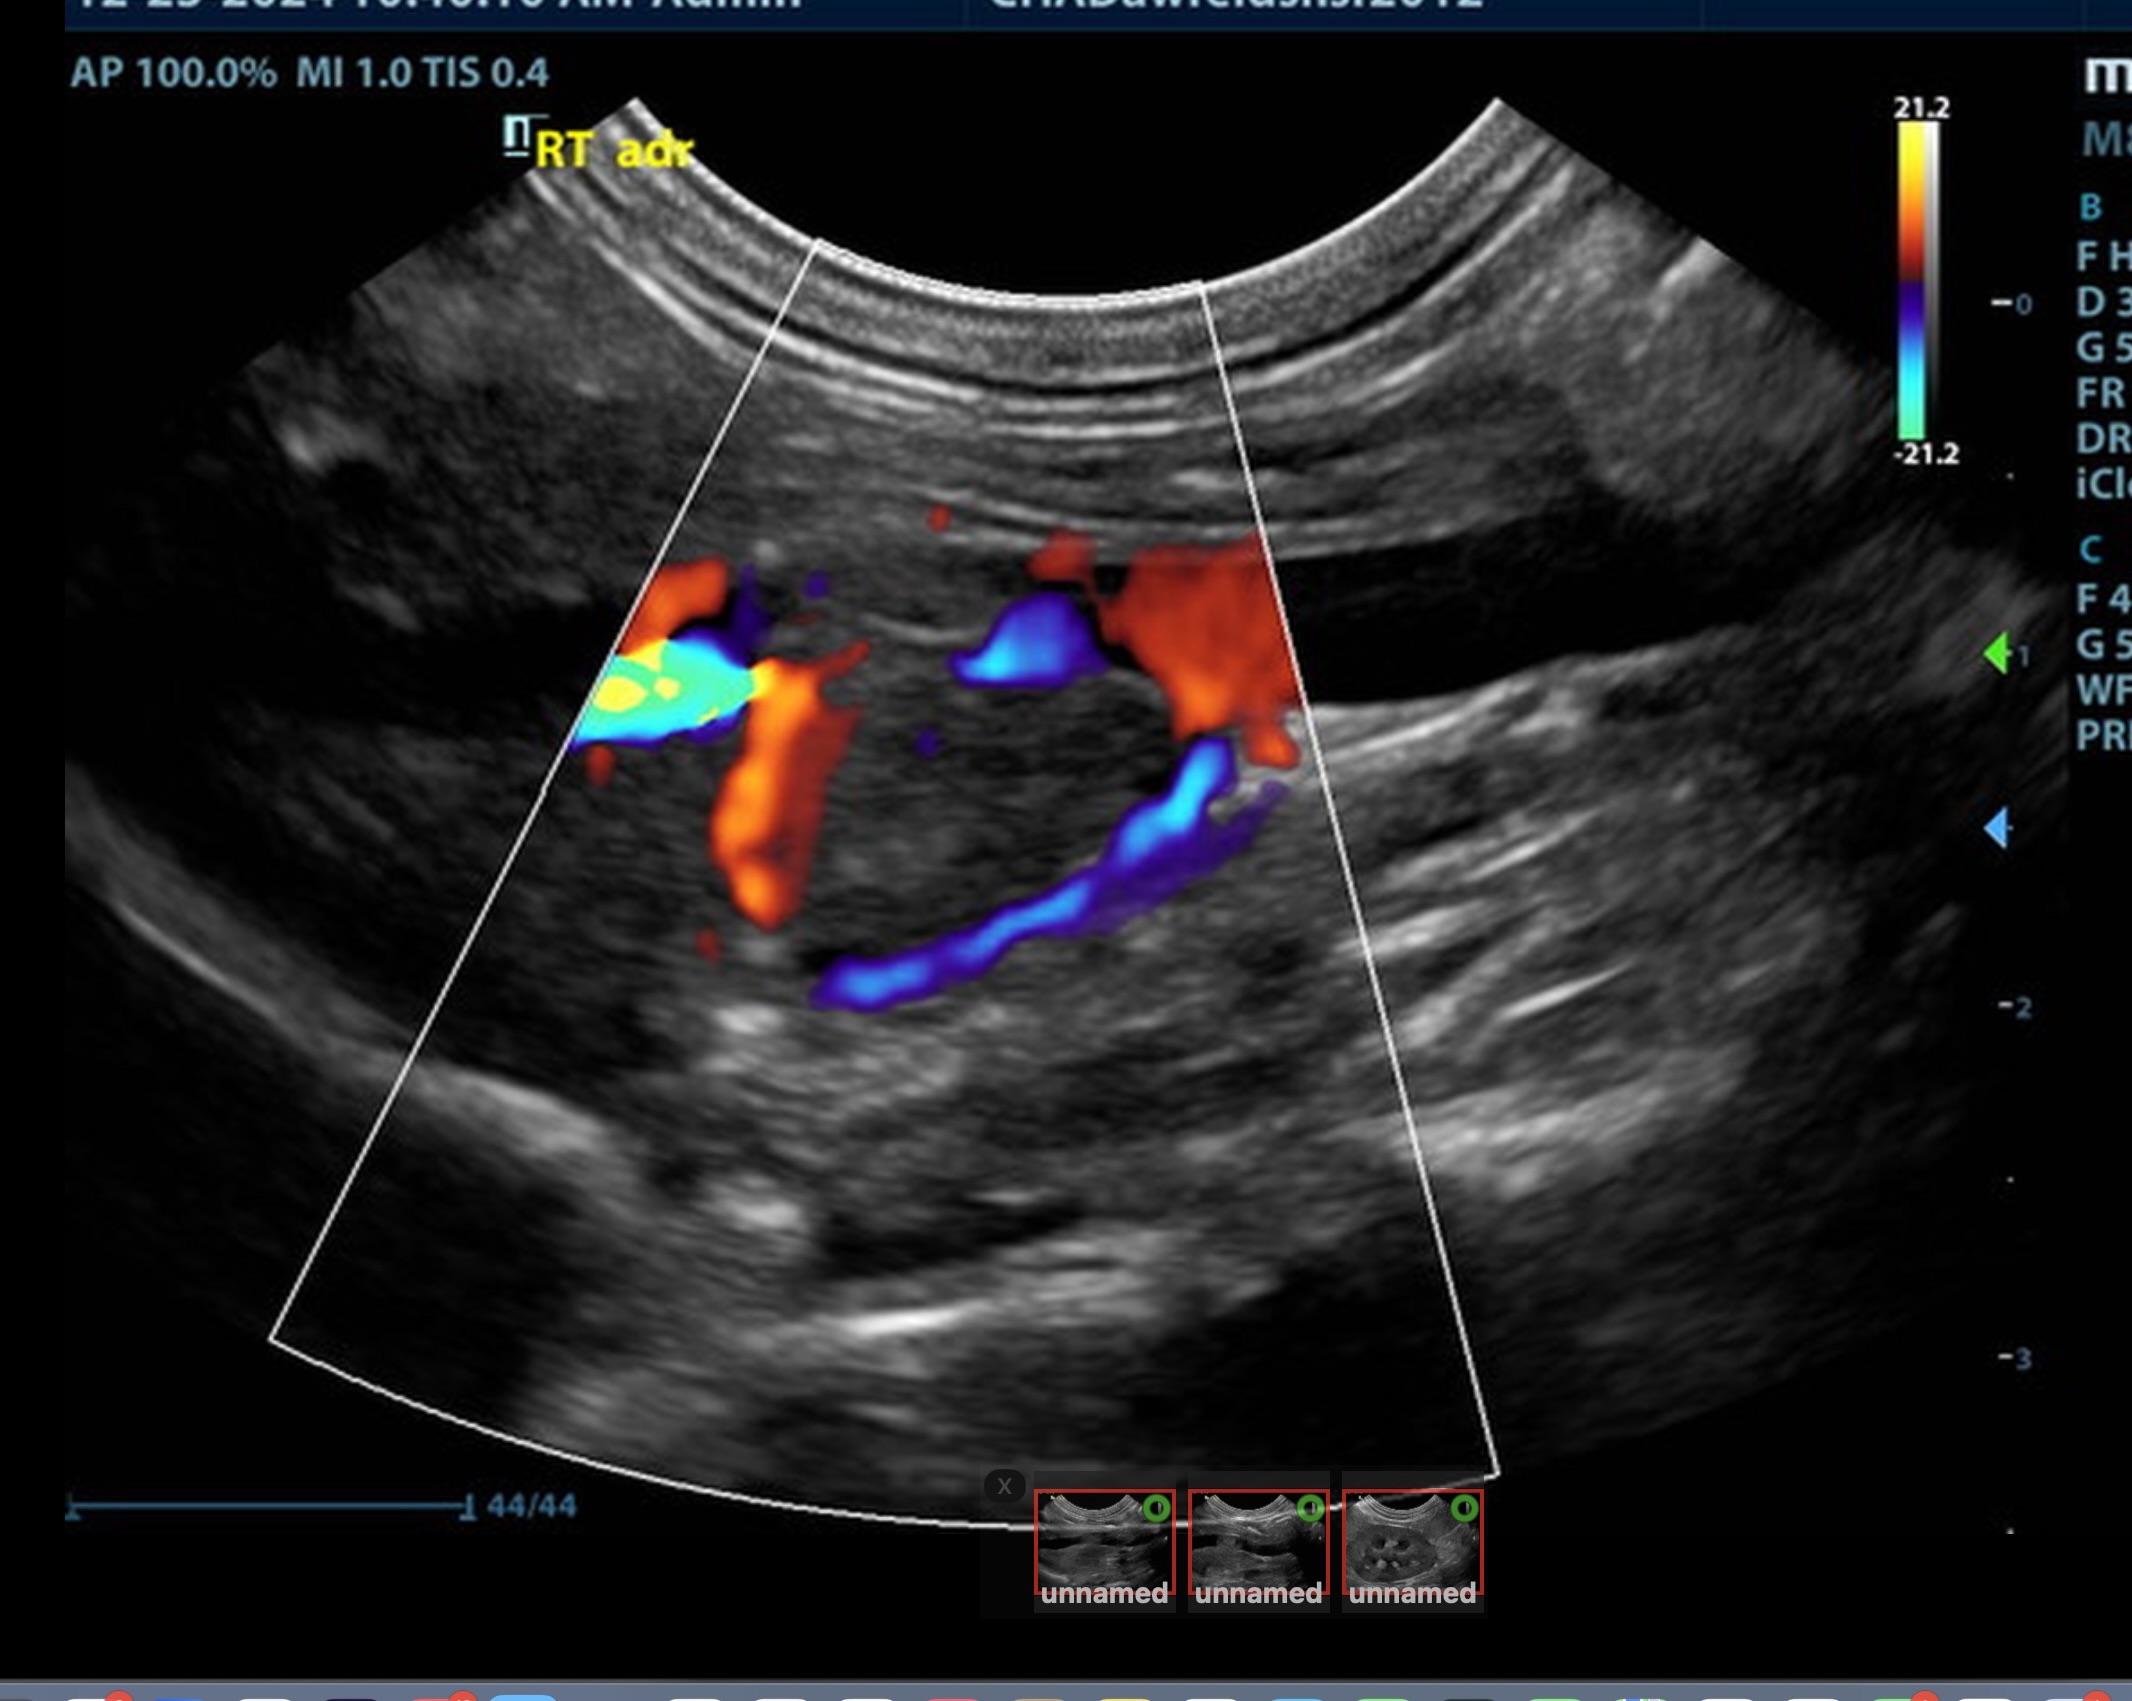

The right adrenal was enlarged and irregular, measuring 0.77 cm at the cranial pole and 0.30 cm at the caudal pole, with a caval invasion of 0.85 cm. Minor areas of mineralization noted. The left adrenal gland was recognized as normal. Mild variable GI thickening and echogenic submucosal changes. Some loss of renal curvilinear patterns regarding the capsule and cortico-medullary junction; increased echogenicity, mineralization.  Some hepatic parenchymal remodeling.

• Invasive right adrenal mass

Surgical consult warranted. The surgeon should be prepared for invasion of the vena cava at approximately 1.0 cm. Assessment of sodium to potassium ratio warranted. If hypokalemia present, aldosterone levels indicated. Serial blood pressures, chest radiographs warranted. No overt evidence of metastatic disease. The right adrenal pathology may not be overtly responsible for the weight loss. Malassimilation/maldigestion panel should be considered.